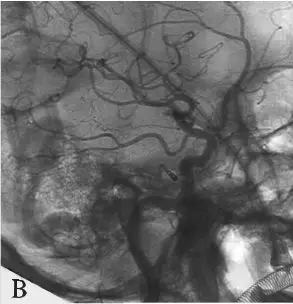

D:右侧椎动脉造影;

DSA:急诊行全脑血管造影提示基底动脉下段可见1枚形态不规则囊性动脉瘤(图18-3B)。三维重建后提示基底动脉下段开窗畸形,动脉瘤瘤颈位于开窗近段分叉处,瘤顶有子囊(图18-3C),动脉瘤瘤颈1.85 mm,瘤深5.45 mm,瘤宽2.77 mm。左侧椎动脉造影提示左侧椎动脉仅供血小脑后下动脉(PICA)区域,未汇入基底动脉(图18-3D)。颈内动脉造影未见明显异常。

D:左侧椎动脉造影提示左侧椎动脉发育不良,仅供血小脑后下动脉(PICA)区域。